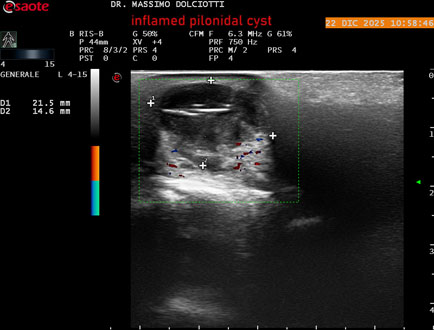

Strumento: Esaote MyLab Eight

Sonda: Lineare Multifrequenza 4-15 MHz

Età Paziente: M 29 anni

Motivazione dell'esame: da 3.giorni dolore, tumefazione ed arrossamento in regione coccigea

Commento all'esame: le immagini ed il video documentano formazione anecogena in sede coccige, delle dimensioni di 24,6 x 18,8 mm, da ricondurre a cisti pilonidale flogosata.

Conclusioni: cisti pilonidale flogosata (inflamed pilonidal cyst).

Presentazione: Dr. Massimo Dolciotti - Ancona